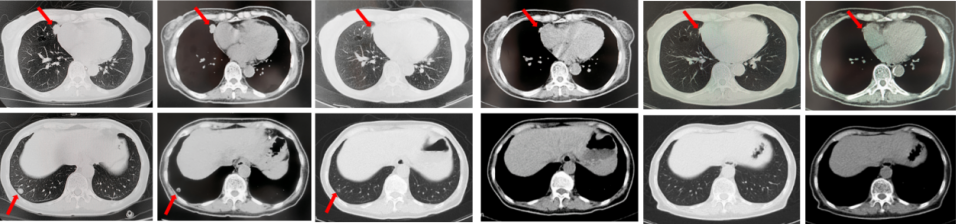

2023年9月复查评效PD。成功入组“一项开放、多中心对比谷美替尼与多西他赛在既往接受免疫治疗和含铂双药化疗后进展的驱动基因阴性且伴有MET扩增的局部晚期或转移性非小细胞肺癌患者中的随机对照III期临床研究”。成功随机到试验组,口服谷美替尼至2024年10月,期间复查最佳评效PR。

图3:A.二线治疗后病情进展,右肺上叶新发肿物较前明显增大,新发无症状脑转移病灶;B.经谷美替尼(300mg po qd)治疗3个月后复查肺内病灶及颅内病灶较前明显缓解

2024年10月复查出现PD,后因患者病情迅速恶化进入肿瘤姑息治疗。该患者的全部诊治经过如图4所示。

67岁女性患者,无既往病史。2019年10月患者因右侧季肋部不适行肺CT提示右肺中叶改变,双肺结节,右侧胸腔积液。行右侧胸腔穿刺引流,送检胸腔积液,液基薄层结果提示肺腺癌。确诊为右肺中叶恶性肿瘤cT2bN1M1a IVA期。基因检测(胸腔积液):EGFR L858R突变。建议患者口服奥希替尼,患者拒绝。2019年11月始口服埃克替尼,定期复查,最佳评效PR(图5)。

图5:A.第2例患者的基线影像资料,由上至下依次为右肺肿物、双肺转移灶及右侧胸腔积液;B.EGFR-TKI一线治疗后最佳复查评效,肺内病灶较前缩小,胸腔积液较前明显吸收。

2020年11月复查评效PD。复测基因检测(血检):T790M阳性,改行奥希替尼治疗,期间评效均为SD(图6)。

图6:A.埃克替尼靶向治疗后病情进展,肺内病灶较前增大,右肺近胸膜处新发转移灶;B.更换三代EGFR-TKI治疗后复查多处病灶未见明显变化。